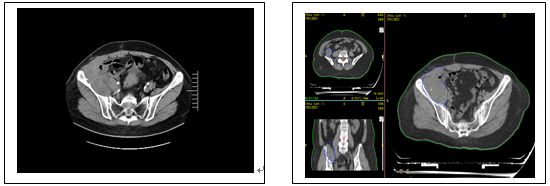

下圖為2021年8月復查MR